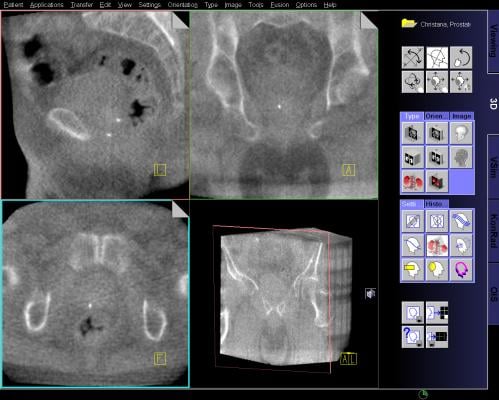

MRI Guided Biopsy: Dr. Samadi's Prostate Cancer Center uses the Uronav Fusion Biopsy System for magnetic resonance imaging (MRI)-guided biopsy. An MRI-ultrasound fusion biopsy involves taking an MRI and then fusing the data with real-time ultrasound images for guidance on biopsy procedures. The UroNav System combines electromagnetic tracking and navigation with an onboard computer and a real-time imaging interface in one mobile workstation. The MR/ultrasound fusion aligns and registers prior diagnostic MR images with real-time ultrasound images.